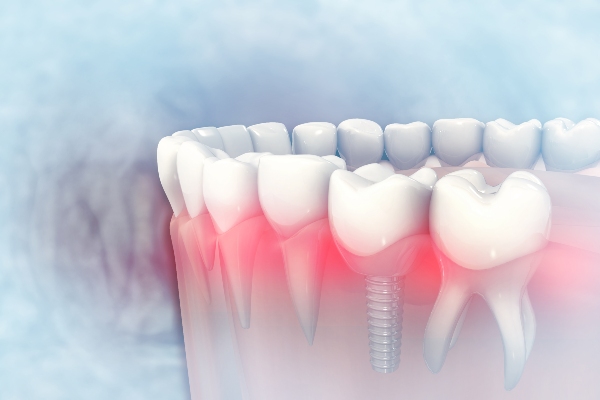

Replacing missing teeth with dental implants can result in a stable and strong bite. It restores the crown and the root. Knowing how this dental replacement system replaces a missing tooth can convince you to set an appointment with your dentist about it. Here are the details about how dental implants can make this happen.

Replacing missing teeth with dental implants can result in a stable and strong bite. It restores the crown and the root. Knowing how this dental replacement system replaces a missing tooth can convince you to set an appointment with your dentist about it. Here are the details about how dental implants can make this happen.

Tooth loss removes the dental root from the jawbone. This means that the jawbone does not have a stimulant anymore. The body does not receive signals to send nutrients to the jawbone for tissue repair. This leads to jawbone loss. Dental implants prevent this from happening.

The dentist cuts through the gum tissue and drills holes into the patient’s jawbone. Applying the titanium rods into the implant holes will follow. Then, the dentist will close the gum tissue over the rods by stitching it. This can help with the implant site’s healing. Dental implants can replace the lost dental roots that stimulate the jawbone. The stimulation signals the body to send nutrients to the jawbone for tissue repair and prevent jawbone loss.

Dental implants are popular sources of support for partial dentures and dental bridges. Each implant replicates a complete dental structure. That is why it looks, functions, and feels like a natural tooth. The titanium rod is the dental root. The dental crown stays on top of the rod by means of an abutment.

The support that dental implants need does not depend on the neighboring teeth. It depends on how the titanium rods merge with the gum tissue and jawbone. A dental implant can function on its own and stand alone. It will not move from its place once the titanium rods become one with the dental components.

It will take about three to five months for the dental implants to finish the fusion and recovery. This creates a strong base for these restorations. This process is osseointegration. Temporary dental crowns can protect the areas while the titanium rods fuse.

After the complete fusion, connecting the abutments will be next. The dentist will cut through the gum tissue to expose the top of the rods. Then, the abutments will attach to them. These titanium parts will connect the dental crowns to the rods. Stitching the gum tissue around the abutments will help these areas heal.

After about two weeks of healing, the dentist will attach the dental crowns to the abutments. The dentist will use strong dental cement in attaching the dental crowns. This will give the patient a stable and strong bite. Dental implants can last for decades with proper care and maintenance.